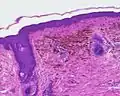

Blue nevus Cellular blue nevus